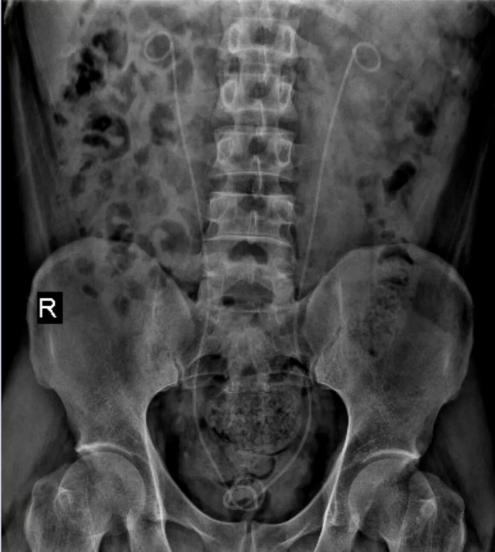

术前与术后对比

自我院引进该技术以来,已在一年内成功为数百例患者解除了结石困扰,其中不乏高难度的双侧结石病例,获得了患者们的一致好评。